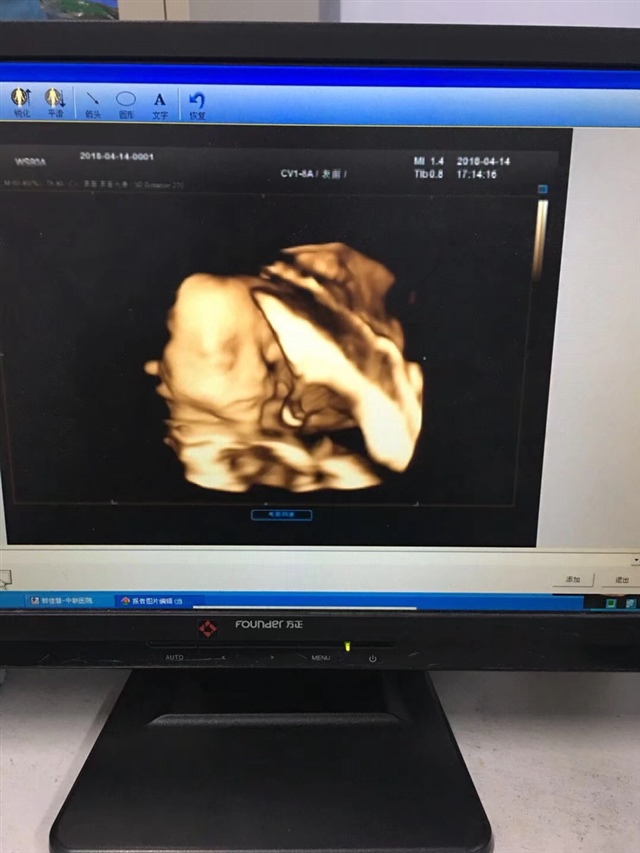

孕36周+5天

肉嘟嘟的,出生有多少斤😄

A??小薇妮[帖主]:6斤8两